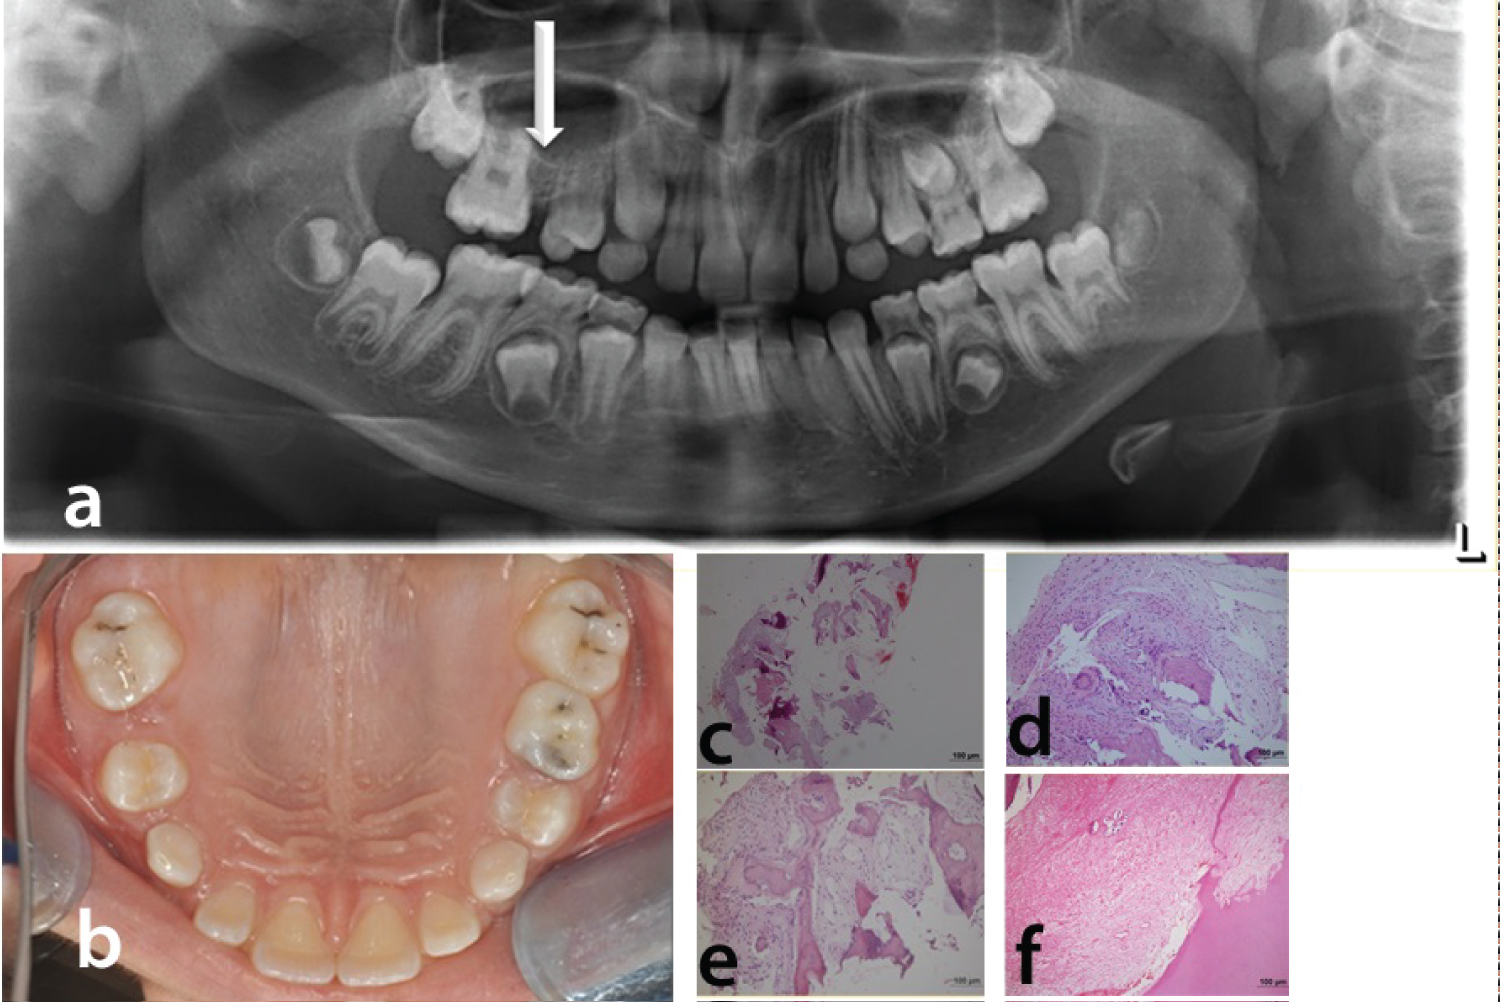

Panoramic radiography of the patient taken 1 year after the beginning of the treatment shows the affected region (Figure 4a). Intra-orally, the edentulous right maxillary alveolar process appeared slightly larger than the left 1 month after extraction of deciduous molars (Figure 4b). Biopsy obtained from the patient showed fibrous connective tissue in the interstitial space between osseous trabeculae. Hard tissue demonstrated irregular lamellar trabecular bone. Some trabeculea were seen as round shaped sementoid tissue similar to fibro osseous lesions (Figure 4c, Figure 4d and Figure 4e). Besides, distrophic calcifications in the pulp were also detected (Figure 4f). Regional odontodysplasia, hemifacial hyperplasia, and monostatic fibrous dysplasia were all considered for differential diagnosis. On the basis of the clinical, radiographic and histologic findings, a diagnosis of HD-SOD was made.

Figure 4: (a) Recent panoramic radiography of the patient taken 1 year after the beginning of the treatment. White arrow shows the affected region; (b) Intraoral photography of the patient; (c) (HE staining x40); (d,e) (HE staining x100): Fibrous connective tissue in the interstitial space between osseous trabeculae. Hard tissue demonstrated irregular lamellar trabecular bone; (f) (HE staining x100): Distrophic calcifications in the pulp tissue. View Figure 4